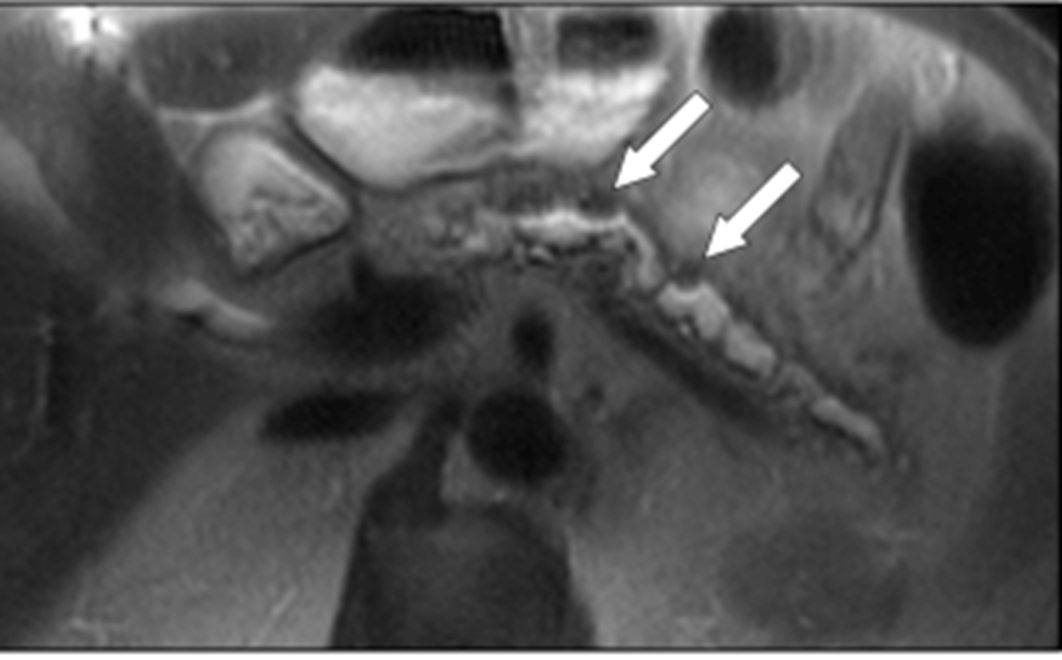

edematous pancreas bc acute pancreatitis

edematous panc with pseudocyst in tail of panc

normal panc with distinct borders